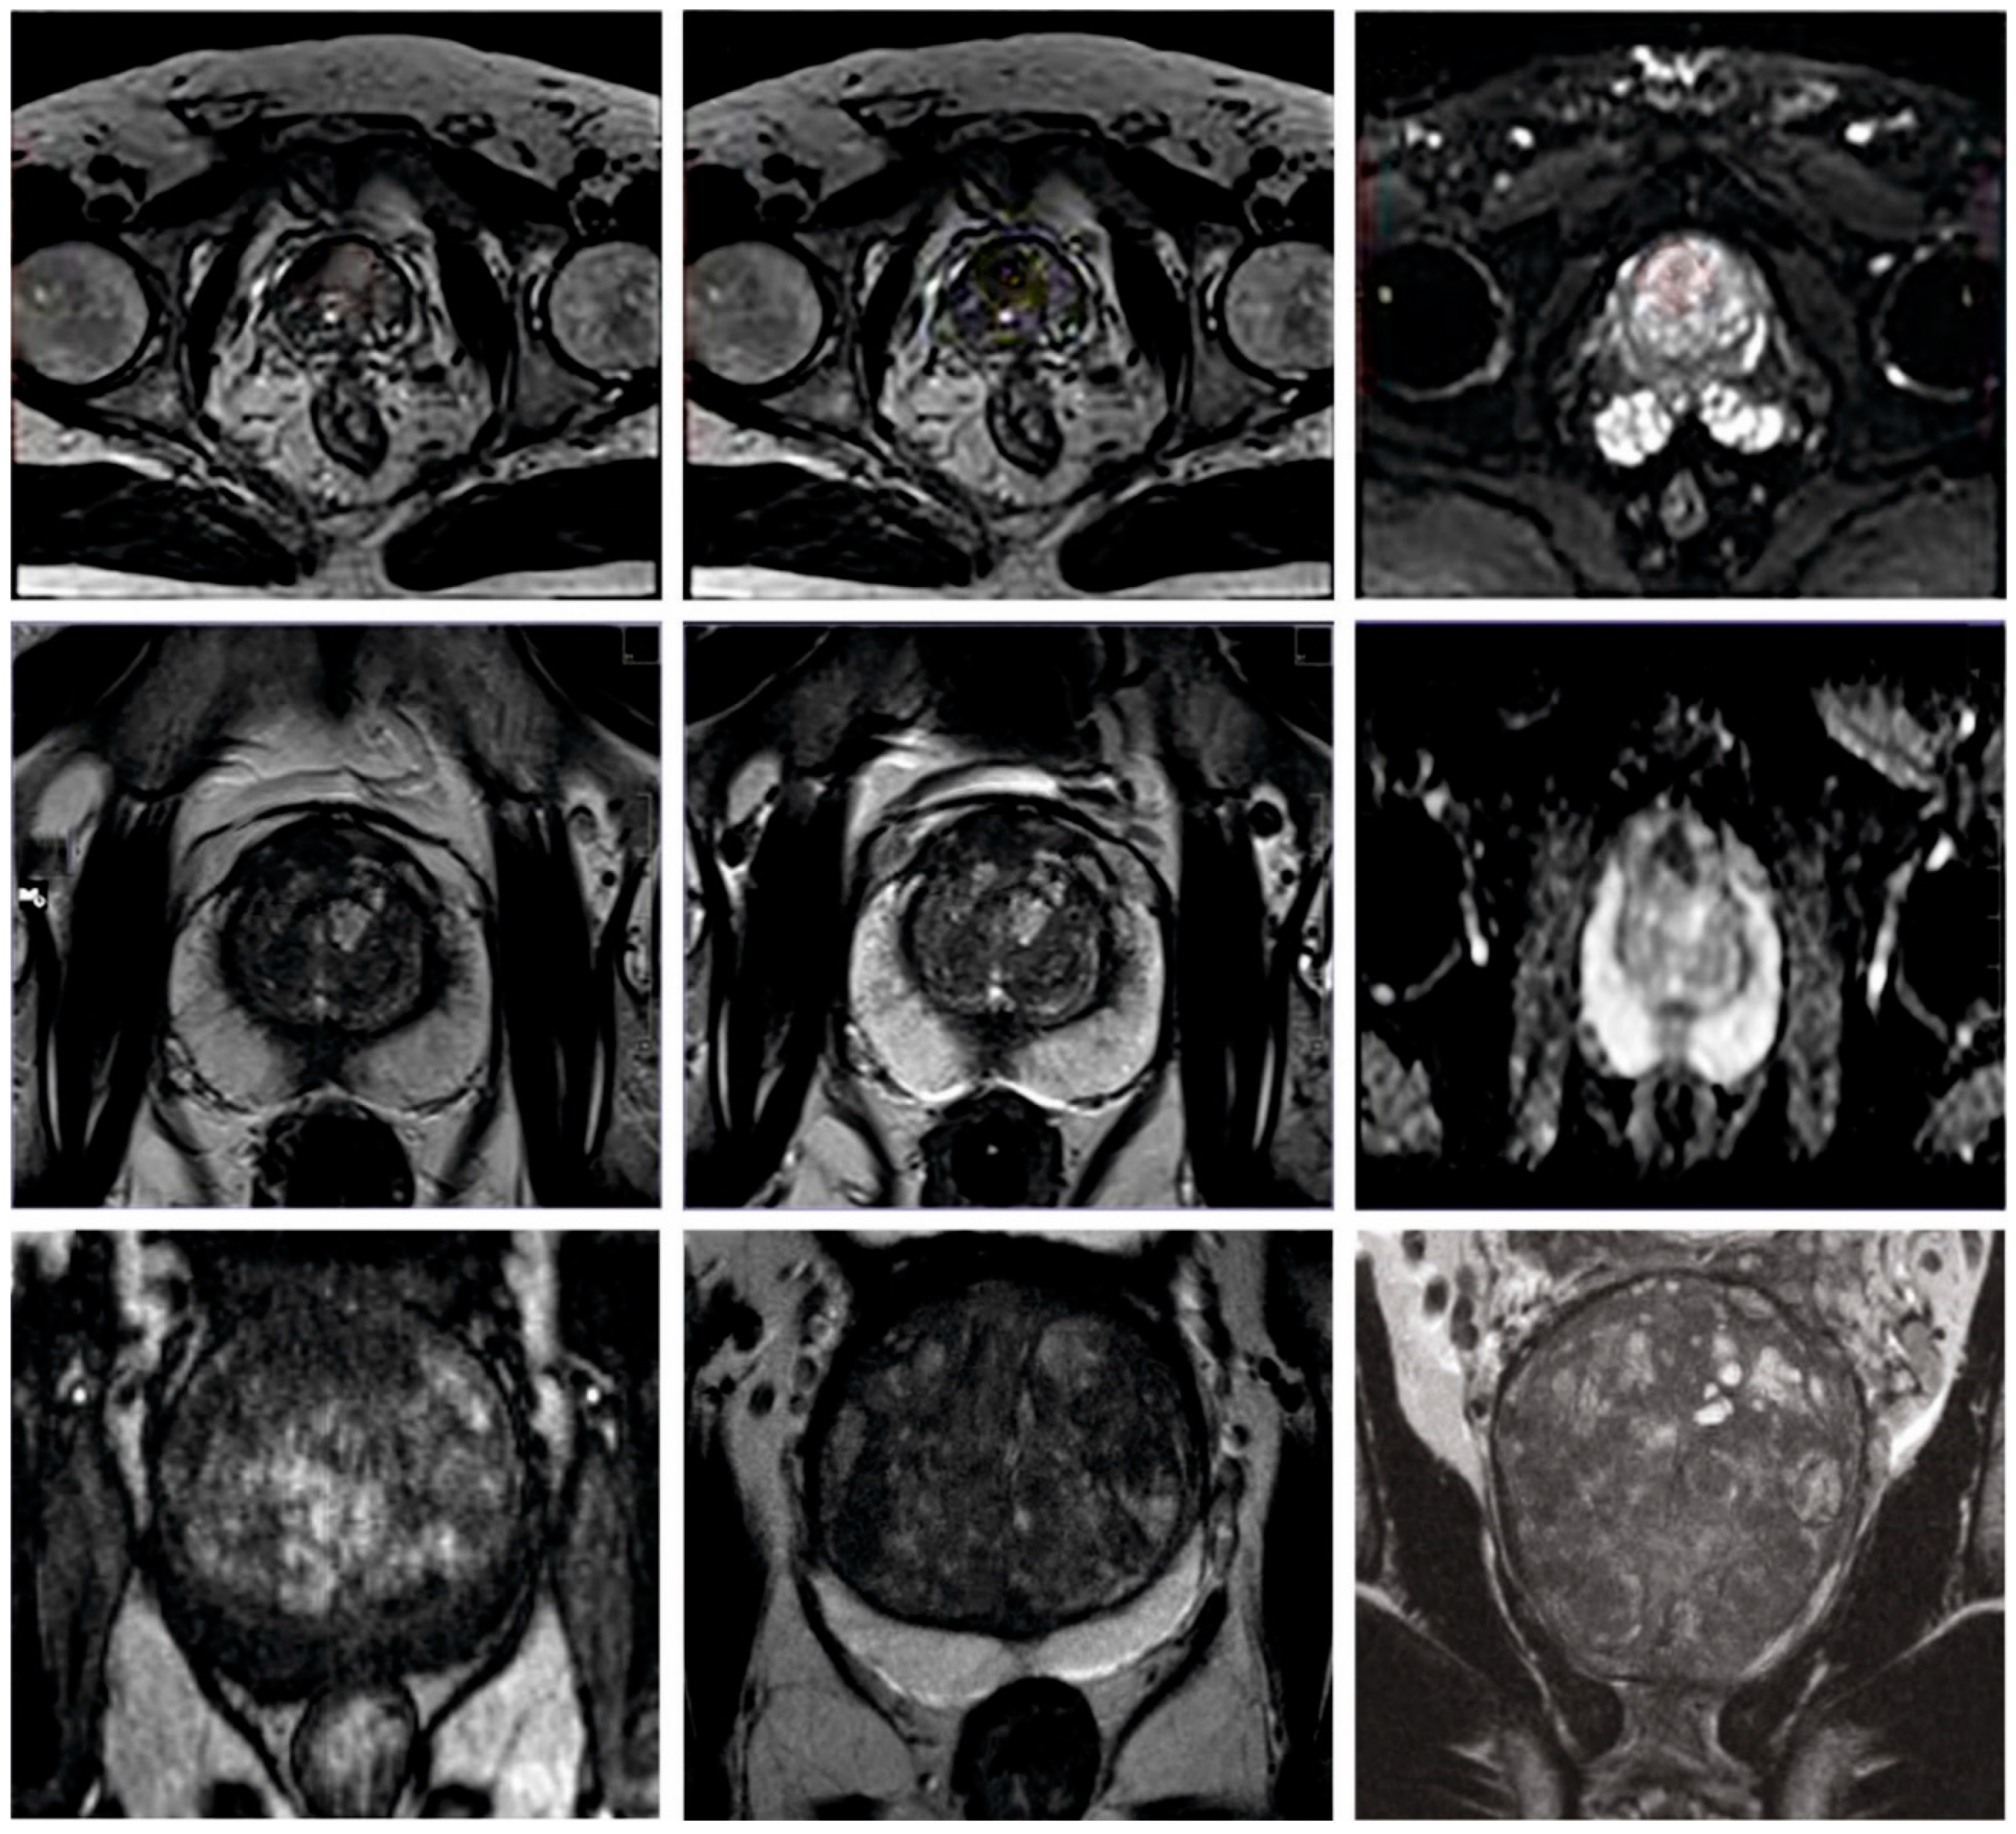

The proposed model was simulated using the Python 3.6.5 tool on a PC configured with the following specifications: i5-8600k, GeForce 1050Ti 4GB, 16GB RAM, 250GB SSD, and 1TB HDD. The parameter settings are learning rate: 0.01, dropout: 0.5, batch size: 5, epoch count: 50, and activation: ReLU. The current section discusses the PCa classification results achieved by the proposed AOADLB-P2C model. The model was tested on a dataset comprising 400 samples under two classes, as defined in Table 1. Figure 3 depicts some of the sample images used in this study.

Figure 3.

Sample images.